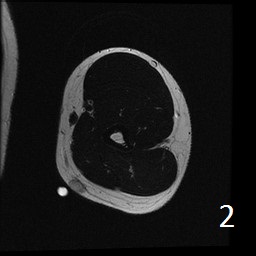

Angiolipoma is a subcutaneous benign tumor, made up of mature fat and blood vessels that often presents as multiple lesions. It sometimes arises intramuscularly. The incidence may be associated with familial heritage, close to 5% of the cases. Angiolipomas often arise in young patients, shortly before puberty, and are rarely seen in younger children or older adults. Angiolipomas often present as single or multiple subcutaneous tender to painful nodules (especially multiple ones). The pain may decrease as the lesion ages. No preference for ages or gender. Sites more commonly affected are the upper extremity and trunk, but rarely can affect head and neck region. MRI shows homogeneous and well circumscribed lesion, with intermediated signal on T1w (Fig. 1) and increased signal on T2W (Fig. 2). On fat suppress sequences the tumor may not suppress completely necause of its vascularity (Fig. 3). There is significant enhancement post contrast images (Fig. 4). On gross pathology the mass is a circumscribed, yellow-red nodular mass due high fat content and blood vessel proliferation. Microscopically, shows mature fat cells separated by branching network of small blood vessels, more prominent in subcapsular areas; there are usually associated fibrin thrombi (important sign). Adipocytes and interspersed vascular structures are seen, lined by elongated endothelial cells. These cells are irregular, and fingerlike extensions surrounded by periytes. Angiolipoma is a benign mass. It does not exhibit aggressive behavior. It rarely shows recurrence after resection. The treatment is complete surgical excision.

Fig. 1-4: Axial MRI of the arm shows a well circumscribed mass with intermediate signal on T1W (Fig. 1), and increased in T2W (Fig. 2). Fig. 3 Axial T1W FS shows a lesion and moderate intense on T1WFS post contrast (Fig. 4).